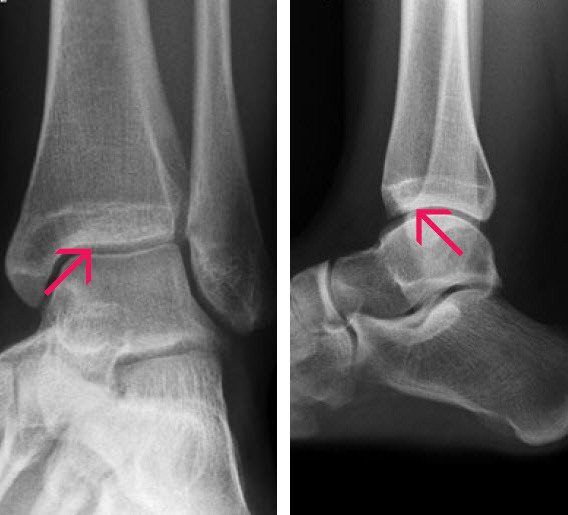

Diagnose

Links: Frontansicht

Rechts: Seitenansicht